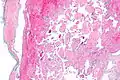

Histopathology Images

Intravascular papillary endothelial hyperplasia is a rare, benign tumor. It may mimic an angiosarcoma, with lesions that are red or purplish 5-mm to 5-cm papules and deep nodules on the head, neck, or upper extremities.[1][2]:592